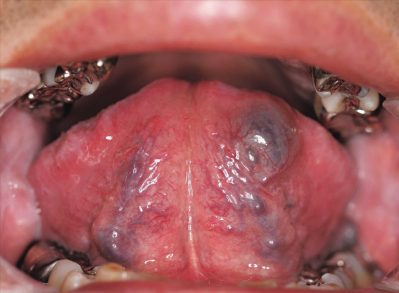

54歳の男性。舌下面の腫脹を主訴として来院した。腫脹は弾性軟である。初診時の口腔内写真と口腔内超音波検査の画像を別に示す。

考えられるのはどれか。1つ選べ。

a. 膿瘍

b. 血管腫

c. 脂肪腫

d. 粘液囊胞

e. リンパ管腫